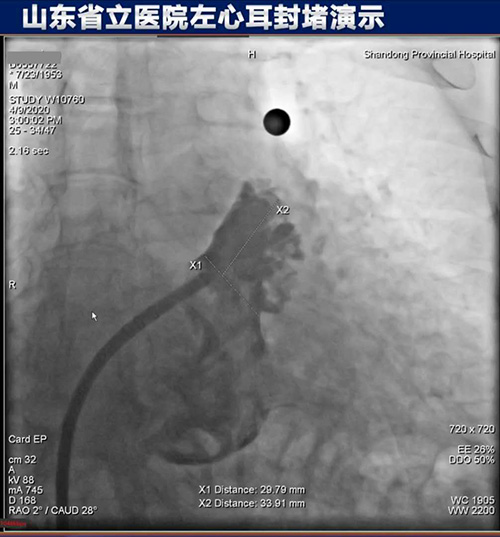

4月9日,山东第一医科大学附属省立医院(山东省立医院)成功举办房颤左心耳封堵手术直播线上演示会。心内科主任医师朱贵月成功实施一例房颤左心耳封堵手术,其首创的RAO 35º+上腔静脉造影指引下房间隔穿刺术,获得业内高度关注。

本次手术通过网络全程直播,从股静脉穿刺、房间隔穿刺、左心耳造影、选择合适封堵器到左心耳完美封堵,手术的每一步关键细节都得到详细讲解,精准解答,并与省内外专家进行线上讨论。直播手术吸引了6000余名专业人士同时在线观看。

房间隔穿刺术是左心耳封堵的关键环节,心脏电生理医师常规选用传统RAO 45º作为穿刺体位,朱贵月主任医师阅读国内外大量关于房间隔倾斜角度的文献资料,结合临床介入操作实践,首创RAO 35º+上腔静脉造影指引下房间隔穿刺术,既提高穿刺位点的准确性,又保证手术的安全性,使介入医师大大缩短了手术学习曲线。